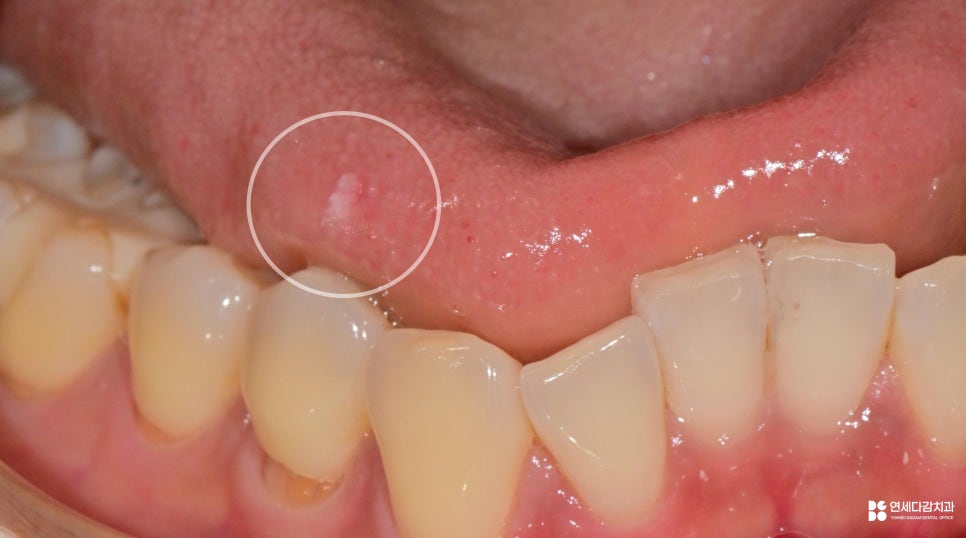

3.절제부터 생검까지

병변 조직을 절제하고 생검을 의뢰를 합니다.

절제 자체는 대부분은 간단하게 끝납니다.

병변의 크기, 위치, 의심 소견에 따라

방법의 선택이 달라집니다.

요즘은 레이저 장비를 활용한 시술도 많습니다.

이는 짧은 시간 안에 시술이 마무리되고

출혈이 거의 없어 회복이 빠릅니다.

작고, 전형적인 병변 제거에 적합하죠.

그러나 병변이 평범하지 않은 소견을 보이거나,

크기가 크다면 외과적 절제를 선택합니다.

개롱역 치과 에서 보여드리듯이

조직을 통째로 도려내는 방법으로

온전히 확보할 수 있습니다.

이를 포르말린 용액에 보관하여

검사를 의뢰하게 됩니다.

검사 결과는 보통 1~2주정도 소요되며,

세포 유형과 악성 여부에 따라

후속 조치가 달라지게 됩니다.

개롱역 치과 에서 확인했을 때

결과는 편평 유두종으로 진단됩니다.

편평 유두종은 HPV에 의해 발생하는

한 형태로 양성 병변에 해당됩니다.